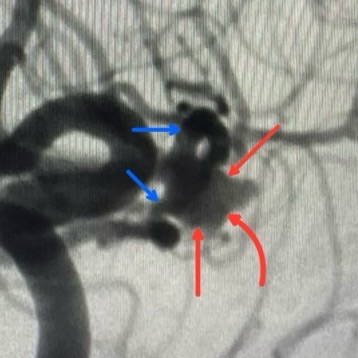

في الصور اللي قدامكم، أنا مشاور على التمدد الشرياني بالأسهم الحمراء 🔴.

والصور دي معمولة بتقنية 3D rotation اللي بتوفرها أجهزة القسطرة الحديثة، ودي تقنية بتورّي لنا التمدد من كل الزوايا، علشان نفهم شكله بدقة، ونعرف فين الرقبة، وفين مكان خروج الشرايين منه.

هتلاقوا كمان سهمين زرق 🔵… دول بيوضحوا الشريانين الطبيعيين اللي طالعين جنب التمدد مباشرة. التمدد ده طالع من منطقة تفريعية بين الشريانين، وده معناه إن أي خطأ بسيط ممكن يؤدي إلى قفل أحد الشرايين… وممكن ده يسبب جلطة في المخ.